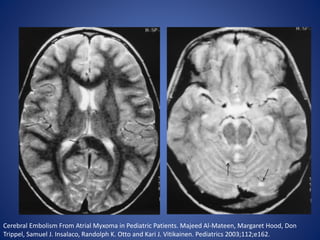

Cardiac diseases

• Cardiac disorders are the most common cause of ischemic stroke

in children and account for up to 50% of strokes.

• The risk of stroke in children with congenital heart disease is

related to the abnormality, diagnostic and surgical procedures,

and associated genetic or acquired factors that predispose

children to thrombosis.

• Cardiac disorders can lead to the development of intracardiac

thrombi that may embolize to the brain or can lead to

thrombosis in cyanotic patients with anemia

Cerebral Embolism From Atrial Myxoma in Pediatric Patients. Majeed Al-Mateen, Margaret Hood, Don

Trippel, Samuel J. Insalaco, Randolph K. Otto and Kari J. Vitikainen. Pediatrics 2003;112;e162.

Cardiac diseases • Cardiacdisorders are the most common cause of ischemic stroke in children and account for up to 50% of strokes. • The risk of stroke in children with congenital heart disease is related to the abnormality, diagnostic and surgical procedures, and associated genetic or acquired factors that predispose children to thrombosis. • Cardiac disorders can lead to the development of intracardiac thrombi that may embolize to the brain or can lead to thrombosis in cyanotic patients with anemia

• 12.

Cerebral Embolism FromAtrial Myxoma in Pediatric Patients. Majeed Al-Mateen, Margaret Hood, Don Trippel, Samuel J. Insalaco, Randolph K. Otto and Kari J. Vitikainen. Pediatrics 2003;112;e162.